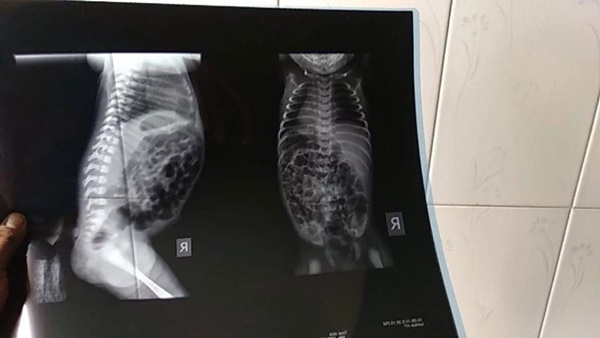

Hình ảnh phim chụp Xquang của bé gái.

Bác sĩ Akash cũng cho biết, ông đã cắt bỏ nó thành công bằng một cuộc phẫu thuật, sau khi chụp X-quang và làm các xét nghiệm cần thiết. Cũng theo lời bác sĩ, tại Bangladesh trước đấy chưa ghi nhận trường hợp tương tự, nhưng trên thế giới đã có khoảng 35-40 trường hợp. Cái đuôi dài nhất được biết đến là của một người đàn ông sống tại Ấn Độ, dài 33cm.